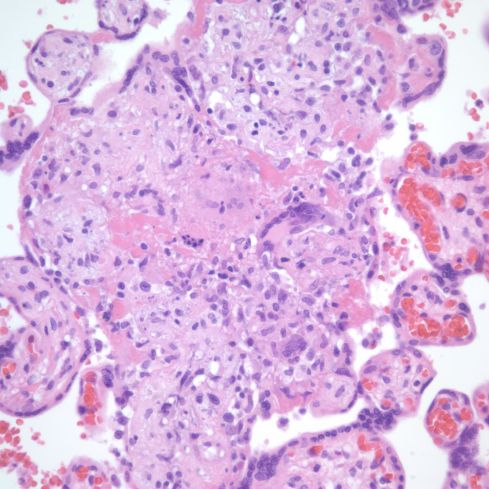

Fig 28) There is core of villi enmeshed in a basophilic matrix surrounded by villi demonstrating VUE. The rectangle is shown at higher magnification in the next figure. (H&E, 4X)

Fig 29) At higher magnification, the basophilic matrix can be seen to be similar to the fibrinous fibrinoid matrix of perivillous fibrinoid deposition with the addition of numerous inflammatory nuclei from perivillus and subsyncytial inflammatory cells. (H&E, 20x)

Fig 30) Another similar focus of enmeshed villi with VUE in another area of the same placenta as figure 5609. (H&E, 4x)